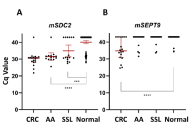

This article belongs to the special issue Global Perspectives on the Clinical Diagnosis, Treatment, and Functional Cure of HIV Infection in the Post-ART Era Analysis of SDC2 and SEPT9 promoters methylation in plasma cfDNA to detect colorectal and precancerous lesionsOpen AccessOriginal ArticleAim: Analysis of circulating free DNA (cfDNA) is now broadly used to diagnose, assess treatment response, and recurrence of various tumor types. Detection of aberrant cfDNA methylation in plasma [...] Read more.Viktoria Borobova ... Sergey KovalenkoPublished: May 21, 2025 Explor Med. 2025;6:1001322

Analysis of SDC2 and SEPT9 promoters methylation in plasma cfDNA to detect colorectal and precancerous lesionsOpen AccessOriginal ArticleAim: Analysis of circulating free DNA (cfDNA) is now broadly used to diagnose, assess treatment response, and recurrence of various tumor types. Detection of aberrant cfDNA methylation in plasma [...] Read more.Viktoria Borobova ... Sergey KovalenkoPublished: May 21, 2025 Explor Med. 2025;6:1001322